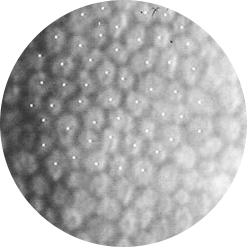

부작용 확률을 낮추고, 수술 성공률을 높이기 위해

수정체 혼탁부위 파쇄시 정교한 파쇄가 필요합니다.

균일하고 정교한

레이저 파쇄